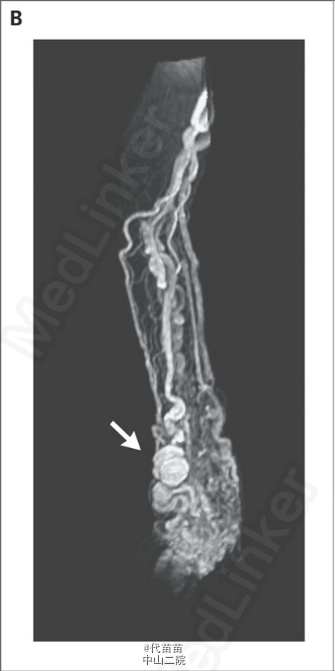

77岁女性,因指尖溃疡求医。患者的左臂自幼年起出现动静脉畸形(如图 A)。 查体发现肥大病变,伴累及手指、前臂、肘部和上臂的巨大动静脉畸形。该畸形为搏动性,伴静脉和动脉扩张和明显震颤。指尖可见小溃疡灶。无心衰表现。针对肘部、前臂和手的磁共振血管造影可见扩张、扭曲的动脉和静脉,已成像的肢体部分可见数处动脉瘤性扩张,伴多发性高流量动静脉短路(如图 B)。帕-韦二氏综合征(血管-骨肥大综合征)的病变包括静脉和毛细血管畸形伴高流量动静脉短路,以及相关肢体的过度增生。多数病例为散发性,但也可能有遗传因素。部分病例由inRASA1突变导致。累及手臂的帕-韦二氏综合征非常罕见,特别是这种程度的血管扩张,推测系病程过长引起的。本病常累及下肢。本例患者拒绝接受手术治疗,对指尖溃疡灶采取加压包扎和局部伤口护理。